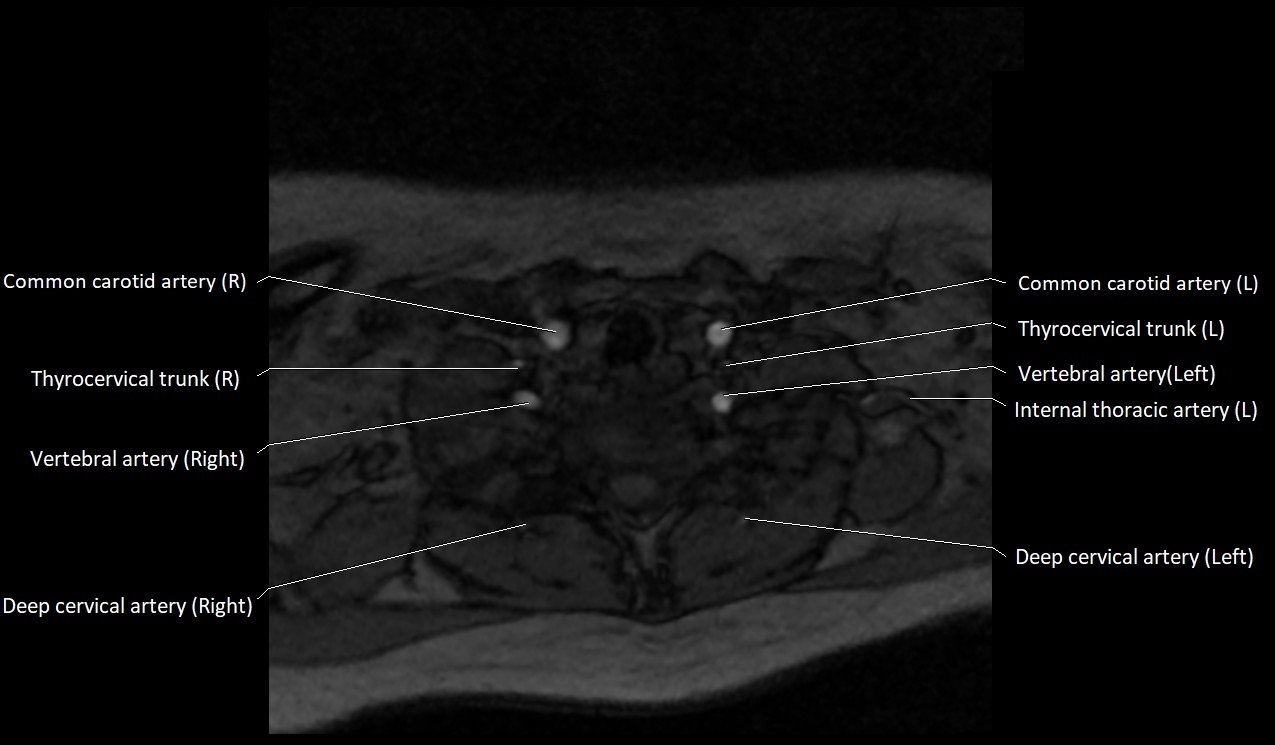

MRI images

image